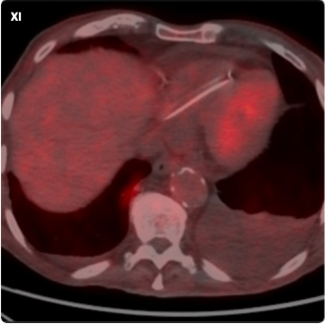

Tomohiro Fujisaki, MD, PhD; Shuichi Yoneda, MD, PhD; Yasuhide Asaumi, MD, PhD; Teruo Noguchi, MD, PhD

A 72-year-old man with coronary artery disease presented to our hospital with exertional angina. He was taking 5 mg of apixaban twice a day for atrial fibrillation.